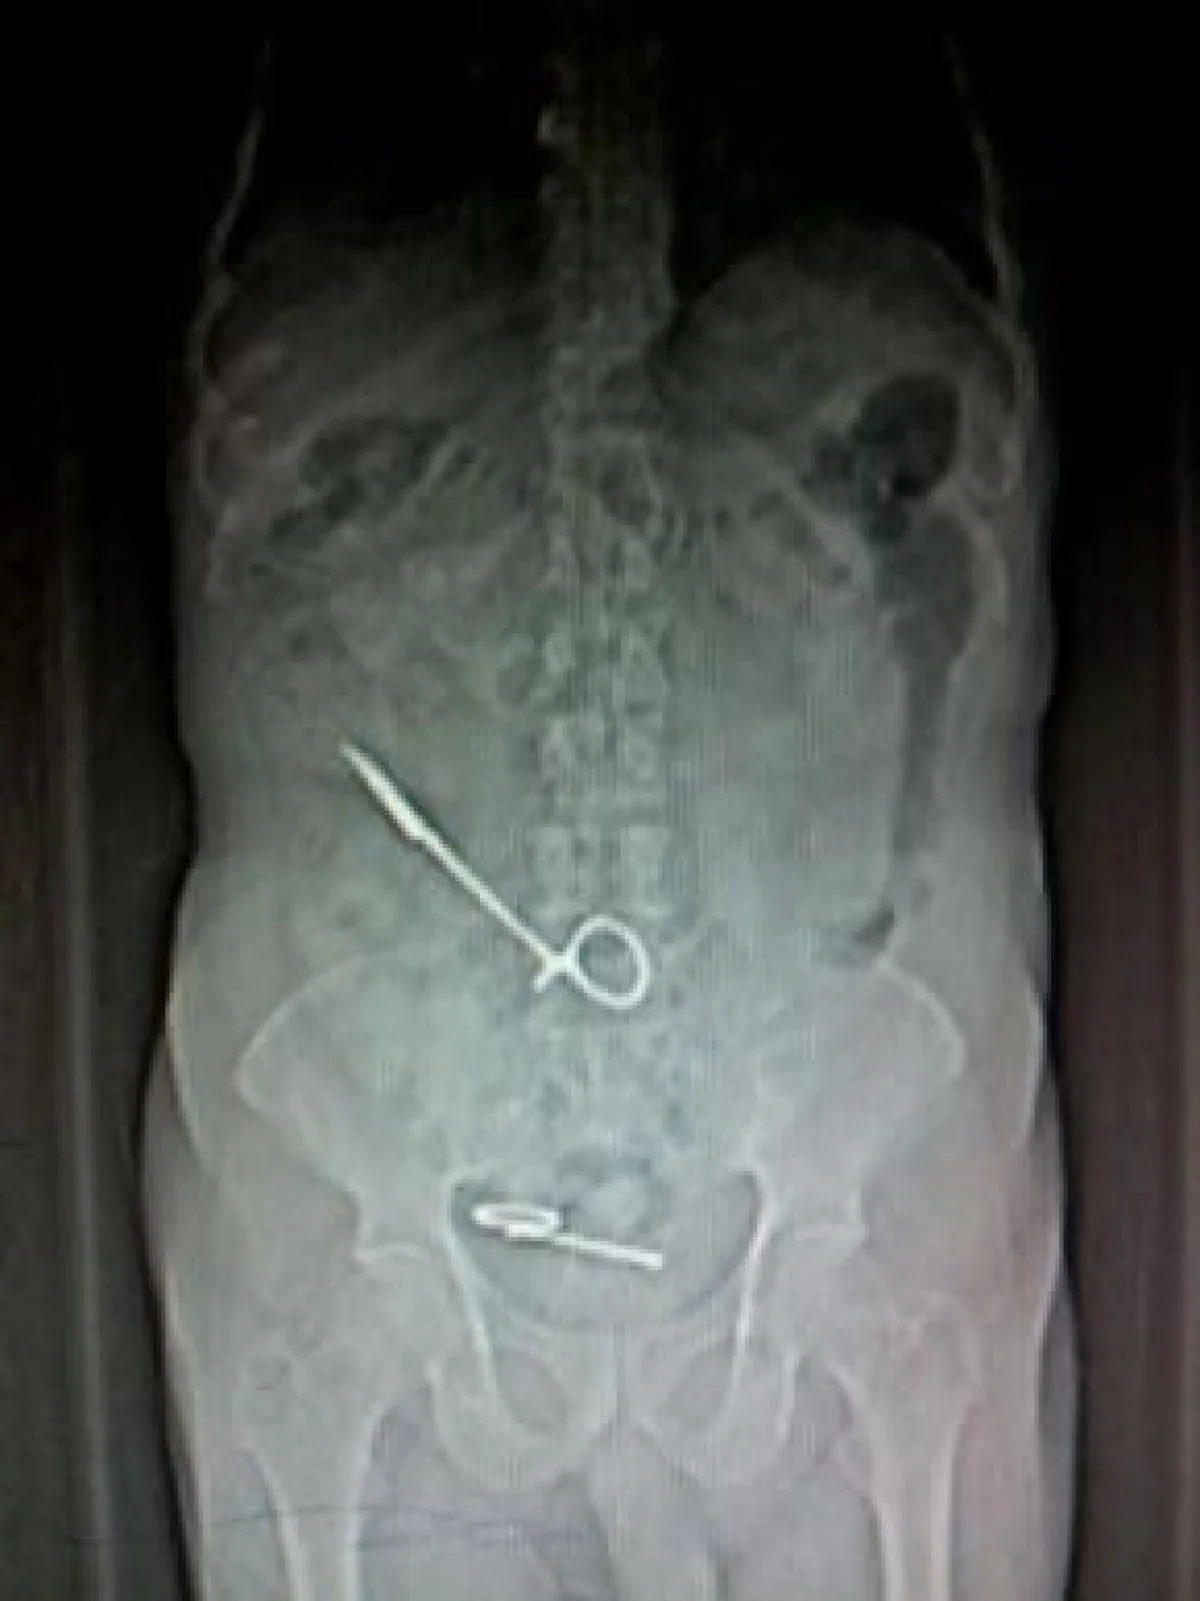

وبحسب ما أوردته صحيفة «سبق» فإنَّ المريض، وبعد خروجه من المستشفى بأُسبوعين واشتداد الألم عليه، توجه إلى مدينة الملك عبد الله الطبية في مكَّة، وبعد إجراء الفحوص الطبيَّة اللازمة كانت المفاجأة وجود قطعتَيْن من مقص طبي مكسور داخل بطنه، إحداهما قريبة من الحالب والأخرى في الجانب الأيمن، فأخضعه الأطباء على الفور لجراحة واستخراج المقص من بطنه.